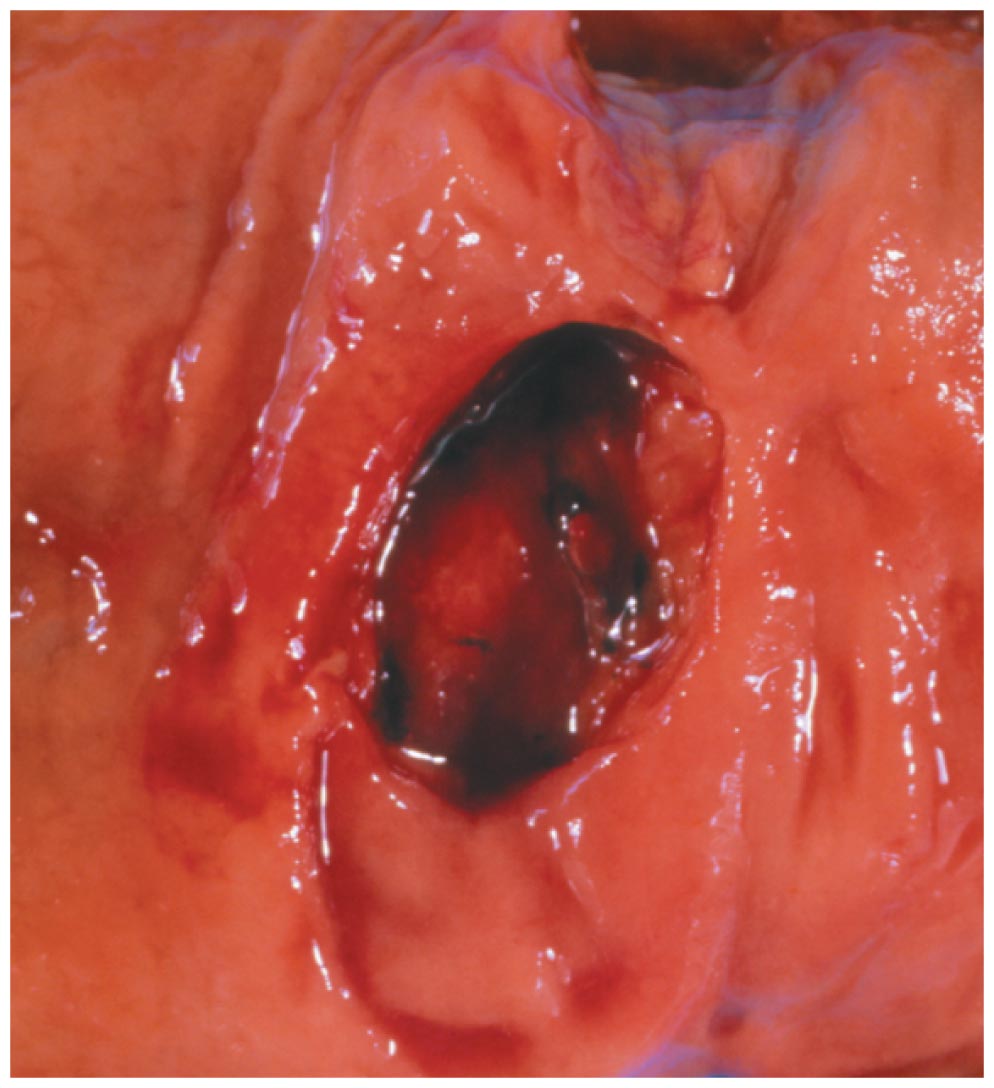

•Peptic ulcers are regions of the GI tract that have been eroded by HCl and pepsin

•The bacterium Helicobacter pylori contributes to the production of both gastric and duodenal ulcers

Peptic Ulcer